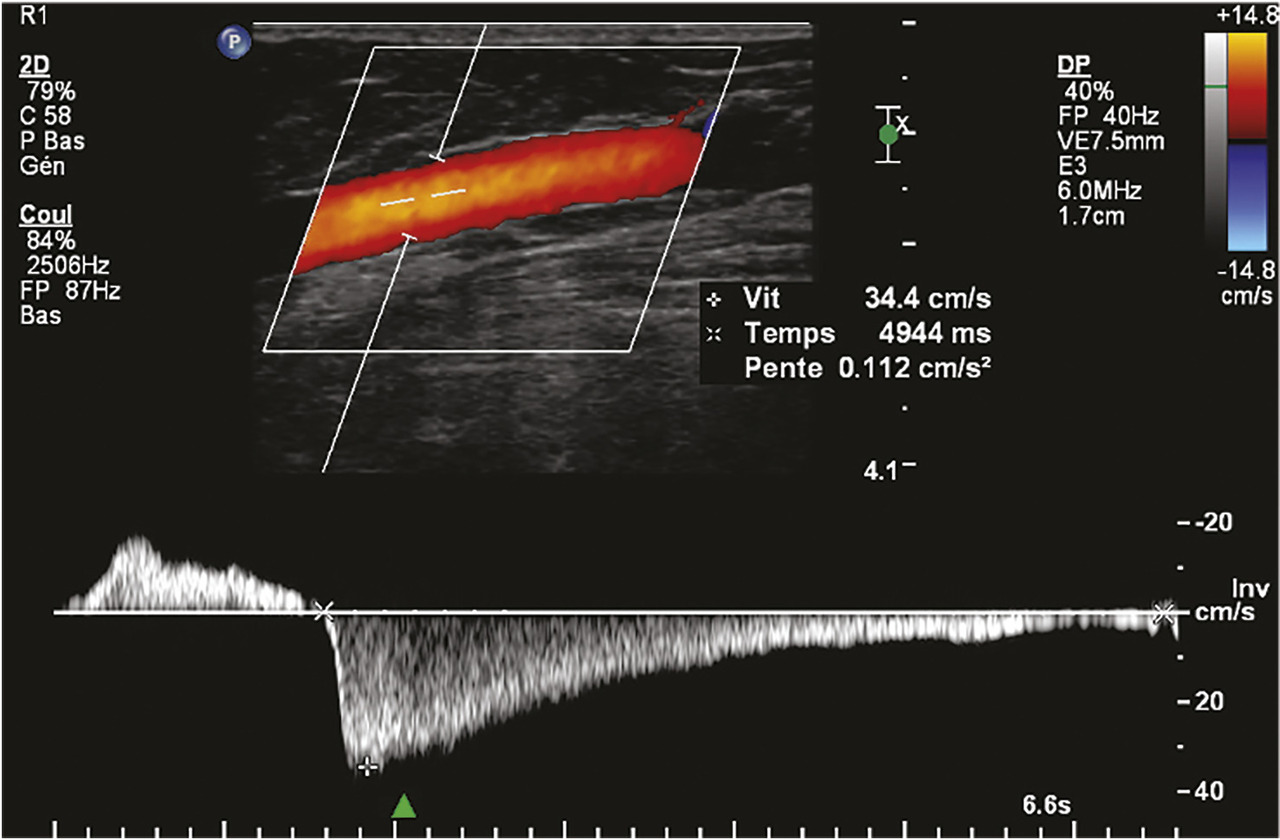

L’écho-Doppler couleur fournit une image des flux qui se superpose à l’image échographique. Cette technique permet d’analyser le sens d’écoulement des flux et leur vitesse de façon semi-quantitative. Par convention, les flux qui se dirigent vers la sonde échographique sont colorisés en rouge et ceux qui fuient la sonde échographique en bleu. Dans les veines saines, le bon fonctionnement du système valvulaire n’autorise qu’un écoulement antérograde en direction du cœur (colorisé en bleu compte tenu de l’orientation de la sonde échographique) dans le système veineux superficiel et profond. Du fait de l’incompétence valvulaire dans les veines variqueuses, on observe, après mobilisation de la colonne sanguine dans le sens antérograde, un reflux colorisé en rouge (fig. 14).

L’écho-Doppler pulsé, qui fournit un spectre précis des vitesses circulatoires, permet d’analyser plus finement les caractéristiques du reflux et d’en faire la quantification (